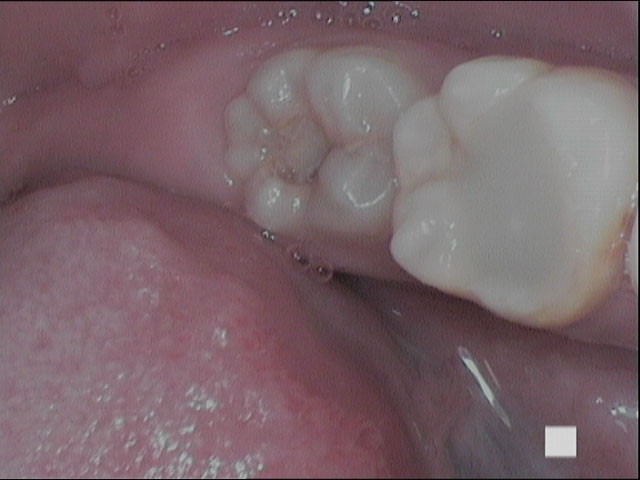

Root Canal Treatment Solution

Untuk setiap kondisi masalah gigi kamu, selalu ada solusi terbaik.

Penanganan yang tepat dengan alat dan teknologi yang memadai menjadikan hasil yang optimal